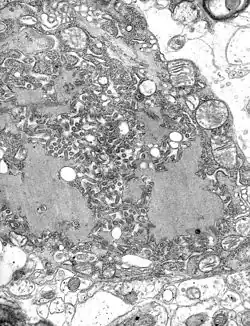

Rabies lyssavirus